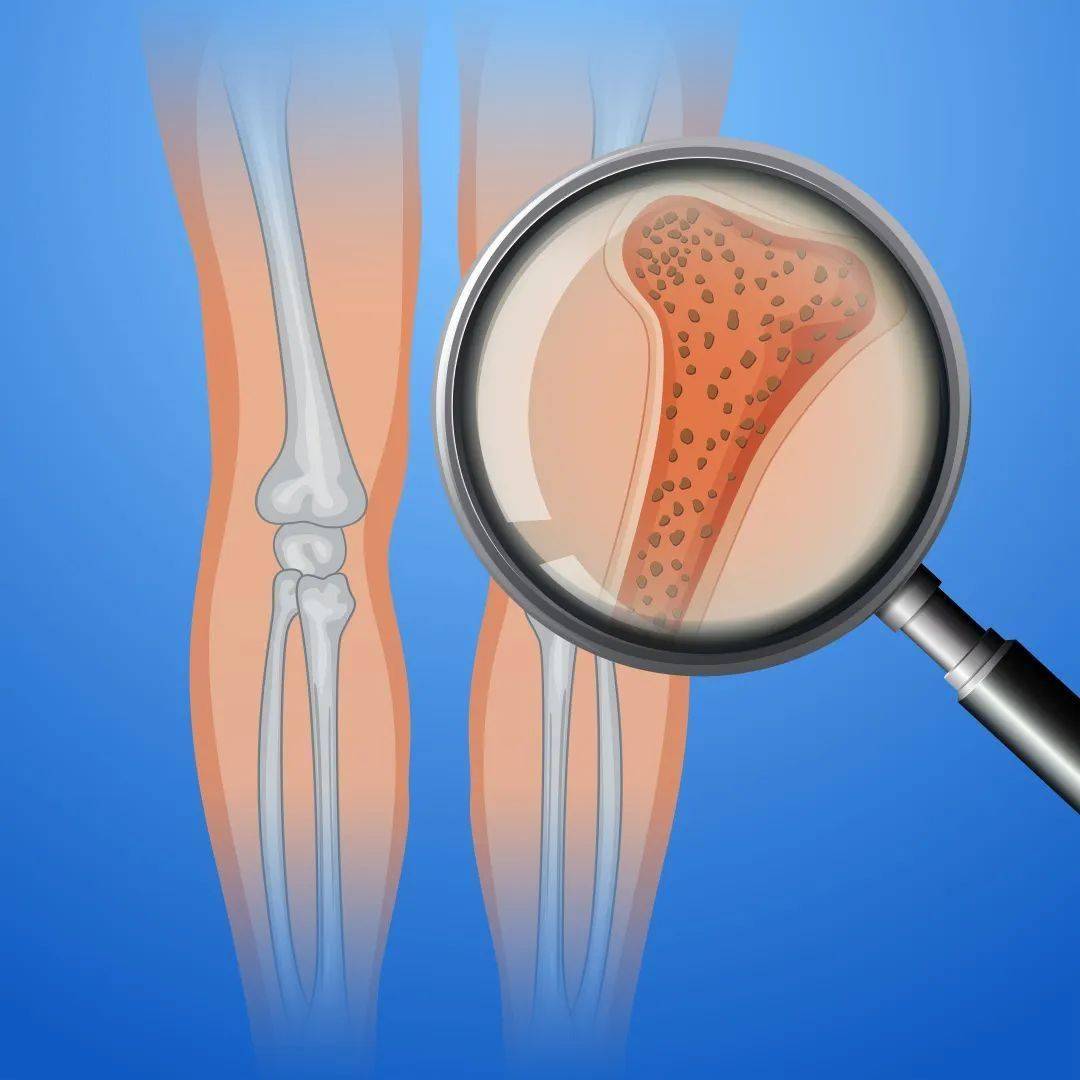

提问 我今年73岁,有哪些检查可以判断我是否会有骨质疏松? 回答 骨质疏松症是一种因骨量低下、骨微结构破坏,导致骨脆性增加、易发生骨折为特征的全身性骨病,与年龄增长有关。 初诊患者需要在门诊由医生问诊

髋关节滑膜炎康复要点包括休息制动、物理治疗、药物治疗、功能锻炼、饮食调理、定期复查等。 1. 休息制动:髋关节滑膜炎发生后,充分休息十分关键。减少髋关节的活动量,避免长时间站立、行走、跑跳等,必要时可